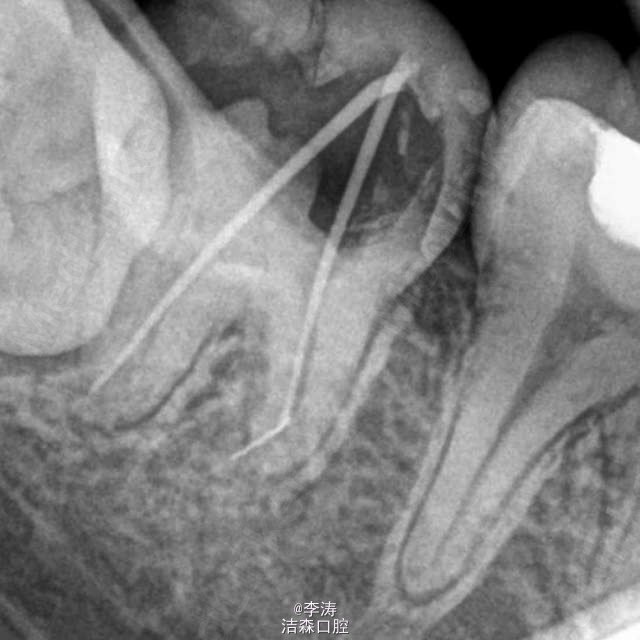

断针推出根尖孔一例

断针出了根尖孔,在预备的时候遇到该不该充填呢?还是充填好后有症状再手术或者拔牙。